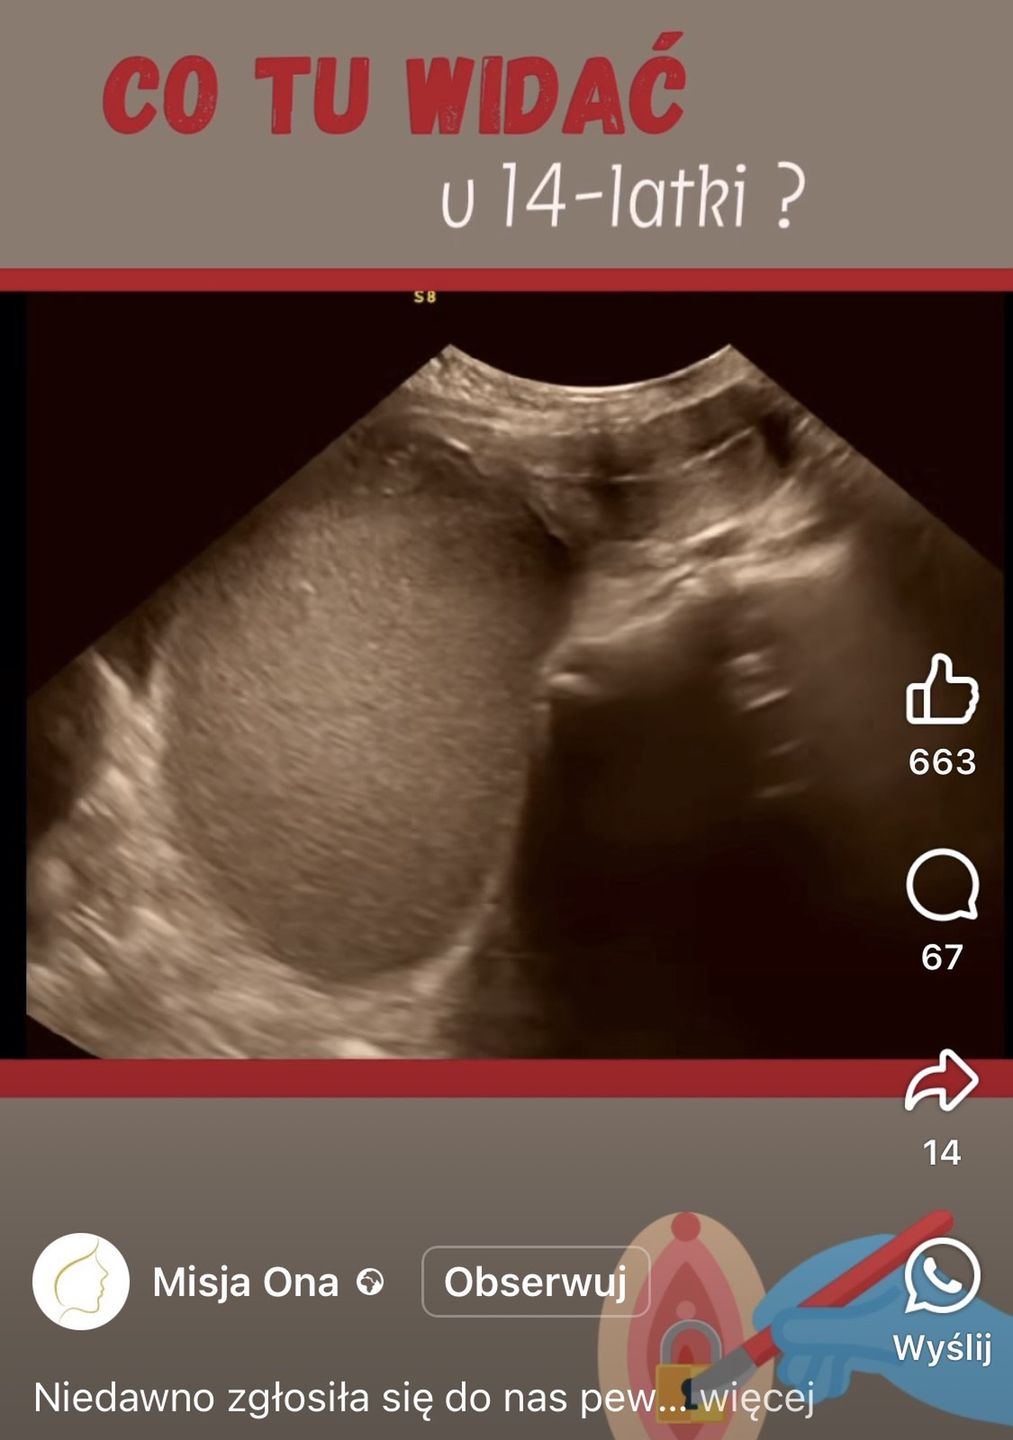

"Co tu widać u 14-latki?" - zapytano pod nagraniem udostępnionym na Facebooku. W komentarzach pojawiały się najróżniejsze przypuszczenia - od ciąży po torbiele. Żadne z nich nie było jednak prawidłowe. Prawda była znacznie bardziej zaskakująca.

Jak się okazało, nastolatka, która przyszła do ginekologa z problemem braku okresu, już od pewnego czasu miesiączkowała. Jak to możliwe? Krew w jej ciele regularnie się zbierała, jednak nie wypływała. Wszystko wyjaśniło USG, które zszokowało lekarzy.

Lekarze opublikowali nagranie z USG 14-latki

Lekarze opublikowali nagranie z USG 14-latki © Facebook | Misja Ona

"Naszym zdziwionym oczom ukazała się kilkunastocentymetrowa zmiana w miednicy mniejszej, wypełniona gęstą treścią. Dziwne. A co w badaniu ginekologicznym? W przedsionku pochwy zobaczyliśmy okrągły, różowy twór wielkości piłki tenisowej! I wszystko już było jasne: to tzw. hematocolpos, czyli krwistek pochwy - napisano na profilu Misja Ona.

W rzeczywistości oznaczało to, że błona dziewicza 14-latki była zrośnięta, a "różowy twór" był wypełniony krwią, która zbierała się co miesiąc. Mogło to stanowić ogromne zagrożenie dla zdrowia oraz życia dziewczyny.